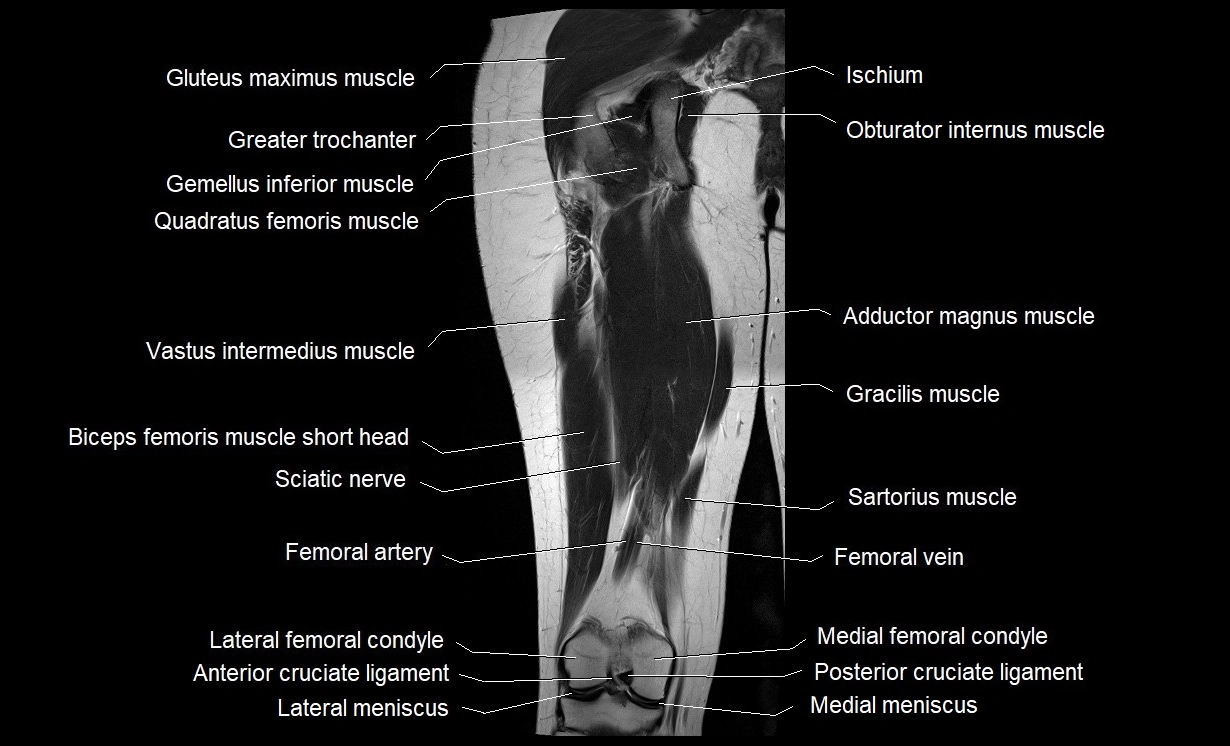

- Anterior cruciate ligament

- Biceps femoris muscle (Long head)

- Biceps femoris muscle (Short head)

- Gluteus maximus muscle

- Gracilis muscle

- Greater trochanter

- Inferior gemellus muscle

- Lateral meniscus

- Medial condyle of femur

- Medial meniscus

- Popliteal artery

- Posterior cruciate ligament

- Quadratus femoris muscle

- Sartorius muscle

- Semimembranosus muscle

- Semitendinosus muscle

- Vastus intermedius muscle